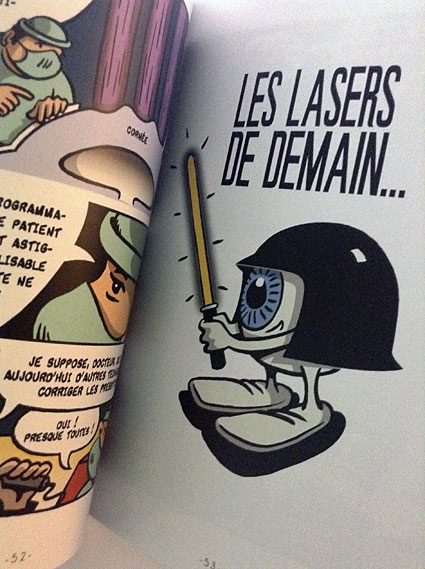

Afin de répondre aux interrogations d'un public de plus en plus intéressé, nous vous proposons cet ouvrage explicatif sous la forme d'une bande dessinée ludique. Cette bédé aborde les troubles de la vision, la chirurgie réfractive (LASIK, PKR et PresbyLASIK), la technique des anneaux et des implants. Cette bébé aborde également l'amblyopie et son traitement orthoptique. Maintenant... à vous de voir !